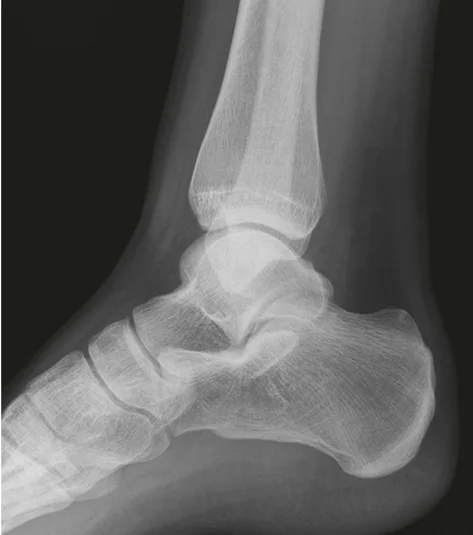

x-ray lat. view of ankle joint

- The image presents two X-ray views of an ankle joint.

- The left image is a plain X-ray.

- The right image is a labeled version of the same X-ray.

Labeled Components:

- Bones:

- tibia

- fibula

- talus

- navicular

- cuboid

- calcaneus

- MT5 (Fifth Metatarsal)

- Other Structures:

- achilles tendon

- Kagerâs Fat Pad

- Joints:

- subtalar joint

- Other:

- mal. tertius

Patient: 32âyearâold male with a severe twisting ankle injury â painful, swollen and unable to stand.

Findings

- Site: lateral malleolus

- Fracture type: simple

- Fracture line: spiral

- Displacement: gap medially

- Special issue: possible ruptured deltoid ligament

Site: Medial malleolus

Type: Simple intraâarticular fracture

Fracture line: Vertical

Displacements

- Gap in joint line

Special issues

- Requires anatomical reduction and absolute stability

- Possible lateral collateral ligament injury